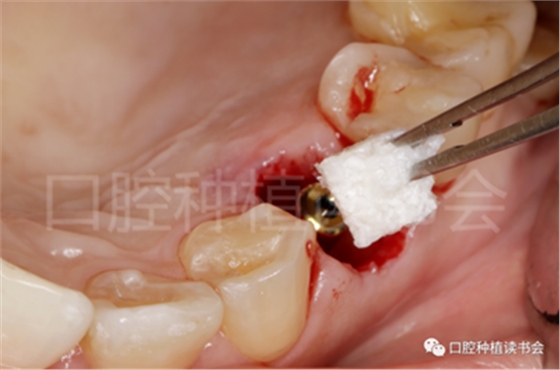

5.3.5 考慮到初始植入扭矩未達到30N.cm,采用外覆”倍菱“膠原蛋白+縫線固定的方式關閉創(chuàng)口的方案(圖18)。

圖18 創(chuàng)口使用”倍菱“膠原蛋白保護,促進愈合。